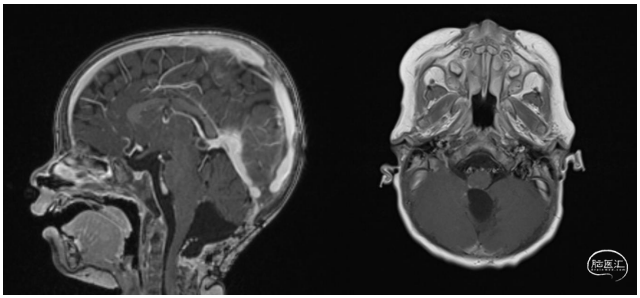

第二次手术较为顺利。在右侧延髓脑桥交界处,残留几毫米肿瘤组织,浸润至第四脑室底部。术中失血量50mL,输注2单位红细胞和1单位血小板浓缩物。术后MRI示,右侧延髓脑桥交界处毫米级强化信号。随后3个疗程化疗,包括卡铂、塞替派和自体干细胞输入。每个疗程间隔28天。到目前为止,总体随访时间为14个月。最后一次随访时,23月龄,没有任何复发迹象,第四脑室底部的强化组织保持稳定。患儿发育正常(图4)。建议局部质子治疗。

图4. 术后14个月的MRI-T1矢状位和轴位像增强成像显示,无复发迹象。